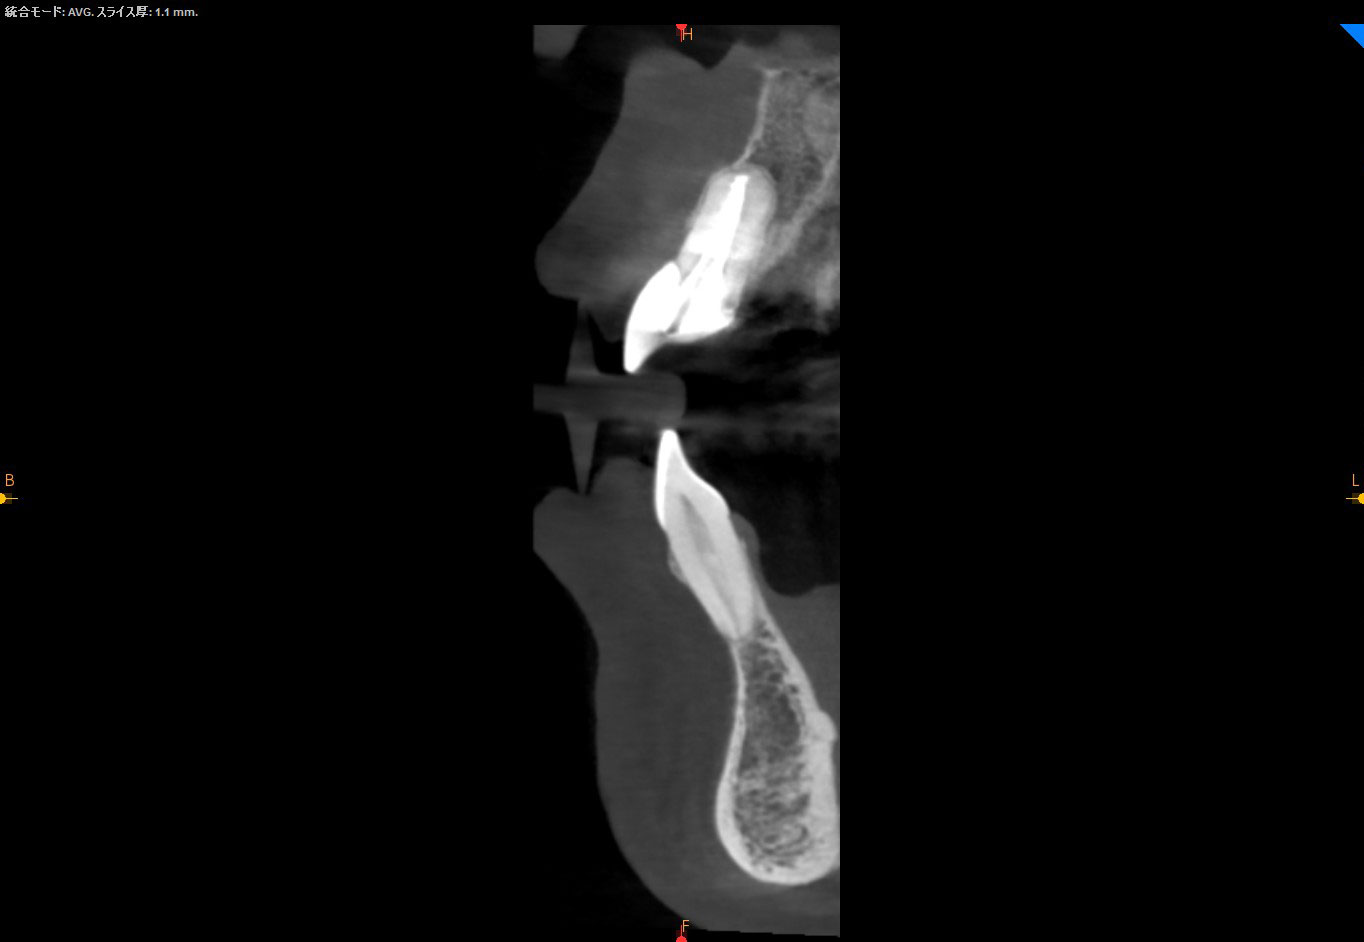

術前CT

過去に歯根端切除を受けた形跡が見受けられますが、完治せず根っこの先に黒い境界明瞭な骨透過像を認めます。